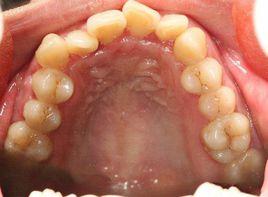

2、牙弓形成和牙排列異常:包括牙弓狹窄、齶蓋高拱;牙列擁擠;牙列稀疏。

3、牙弓、頜骨、顱面關係的異常:包括前牙反合;前牙反合,近中錯合,下頜前突;前牙深覆蓋,遠中錯合,上頜前突;上下牙弓前突,雙頜前突;一側反合,顏面不對稱;前牙深覆合,面下1/3高度不足;前牙開合,面下1/3高度增加。